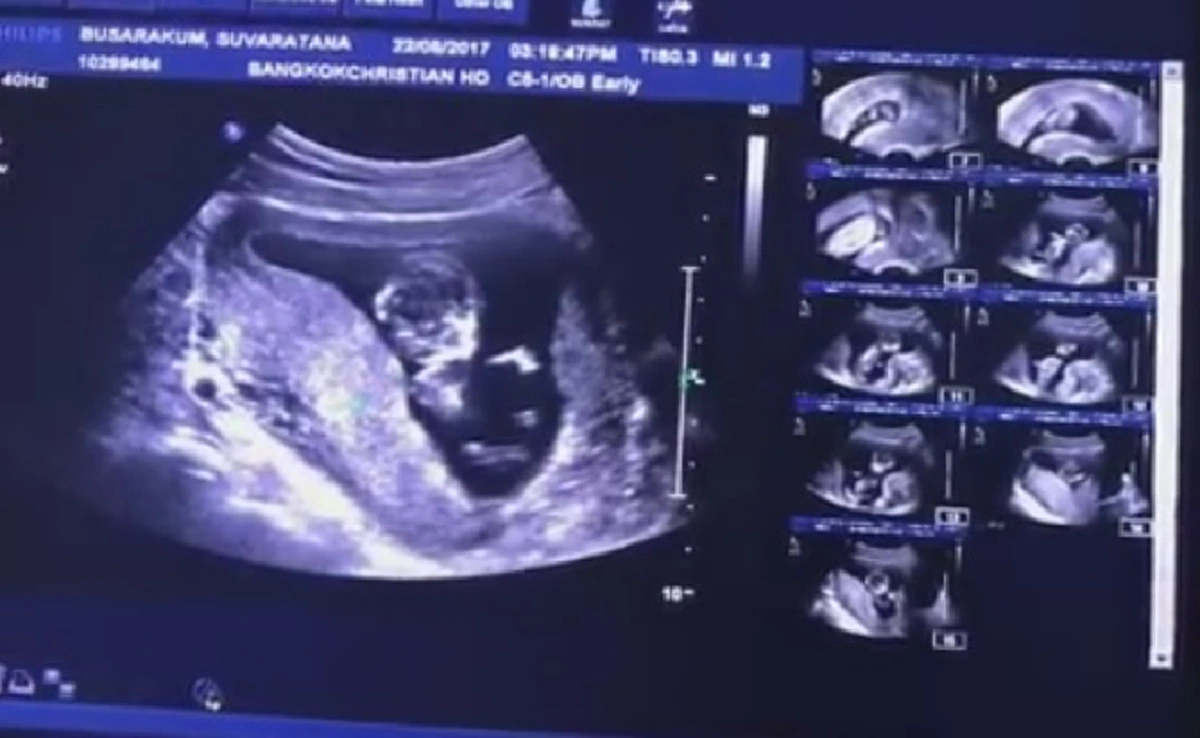

ล่าสุดครอบครัววงษ์คำเหลาได้มีข่าวดีเกิดขึ้นจริงๆ เมื่อสาวเอ็ม ก็ประกาศข่าวดีผ่านเฟซบุ๊กส่วนตัว ว่ากำลังตั้งครรภ์ลูกคนแรก และเป็นหลานคนแรกให้คุณพ่อ "หม่ำ จ๊กมก" ได้สำเร็จแล้ว